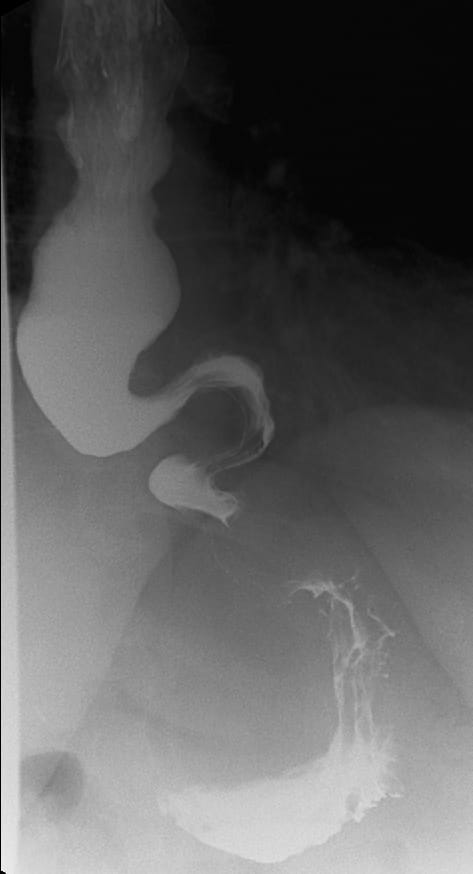

The GI Motility laboratory offers state-of-the-art diagnostic testing of the upper and lower GI tract, such as high-resolution esophageal manometry, pH-impedance monitoring, wireless Bravo pH testing, electrogastrography (EGG), endoFLIP distensibility testing of esophagus and pylorus, antroduodenal manometry, anorectal manometry/compliance and hydrogen breath test for SIBO and carbohydrate malabsorption. The GI Motility lab performed over 2,000 procedures in 2019.